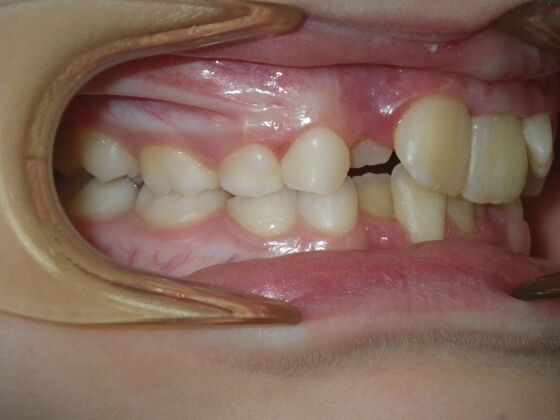

This sweet patient presented with constricted upper and lower arches and blocked out, rotated upper and lower anterior teeth. The upper centrals were leaning backward and had the lower arch captured preventing anterior advancement. Treatment was begun on the upper arch first, followed with placement of lower lip bumper to allow for lateral and anterior development of lower arch. Eventually placed lower brackets with strategic slenderizing of primary teeth to allow permanent incisor to assume their proper placement. All accomplished within 12 months and straight-wire appliances.